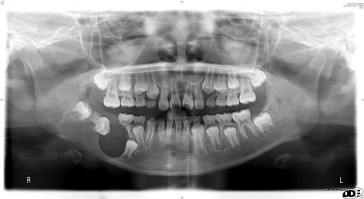

The unicystic ameloblastoma usually appears as a “cystic” lesion with either an intraluminal or an intramural proliferation of the cystic lining:

• Radiographically, it may resemble a well-circumscribed slow-growing radiolucency.

Multicystic ameloblastoma can infiltrate into the adjacent tissue and has the ability to recur and even metastasize:

• Its prevalence is a slightly older age group than the unicystic ameloblastoma.

• Radiographically, the appearance is generally unilocular or multilocular.